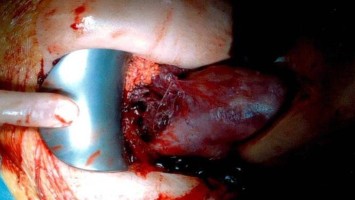

Urogenitale Fistel: So wurde die Patientin endlich beschwerdefrei

Eine 36-Jährige hat bereits mehrere abdominale Operationen hinter sich, um die bestehende Endometriose zu behandeln. Die daraus bedingte Urogenitalfistel und damit einhergehende totale Harninkontinenz konnten bislang nicht erfolgreich behandelt werden.